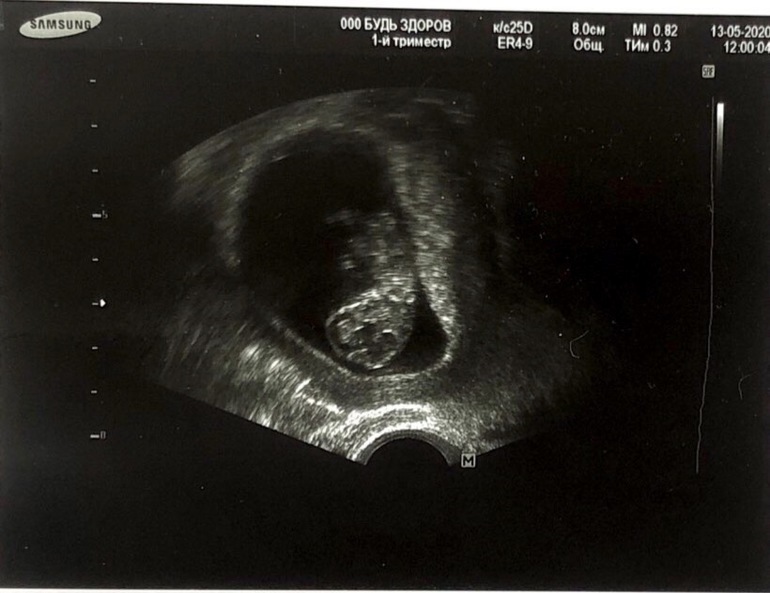

10 недель, УЗИ

Видела половинки мозга, зачатки пальчиков, на картинке тоже можно это увидеть.. Врач показала позвоночник..

КТР - 31 мм; ЧСС плода - 174 уд/мин